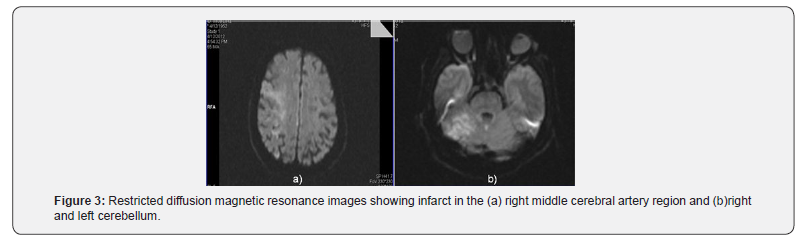

Immediately post-procedure patient became unresponsive and examination revealed dense left sided hemiplegia. Angiogram of the intra and extra cranial vessels did not reveal any obstructive lesion. An urgent computed tomogram ruled out intracranial hemorrhage. The activated clotting time recorded in the cardiac catheterization laboratory was 268 sec. Patient was shifted to intensive care unit and started on supportive therapy. There was no improvement in his clinical state and a diffusion weighted MRI done 24 hrs post procedure showed features of an acute infarct in both cerebelli and the right middle cerebral artery (MCA) territory (Figure 3). Despite optimal care he succumbed to the above complication on the 3rd post angioplasty day.